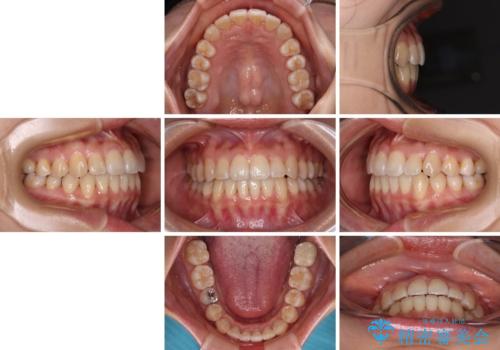

クロスバイトの前歯を改善 ワイヤー装置で楽々矯正治療

- 前歯のクロスバイトを改善したいとのことで来院された患者様です。

舌のトレーニングをしっかりと行っていただき、補綴治療も含めて1年強の短期間で治療を終えることができました。